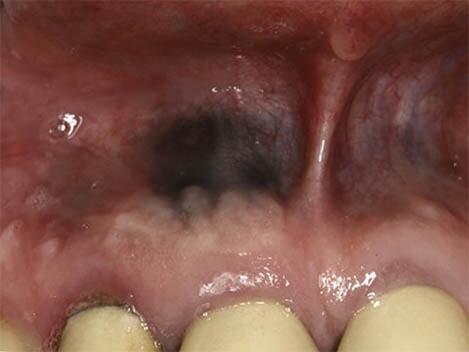

What Causes a Black Spot on Your Gums?

First, we recommend taking a moment to breathe and relax. According to the Oral Cancer Foundation, dark spots rarely indicate a serious condition like cancer and are usually benign. Spots in the mouth are often not fully black but may appear that way as they can be hard to see. We’re here to help walk you through the causes of dark spots in your mouth and what they mean.

Oral conditions like dark spots on your gums have various causes and can be challenging to diagnose. These spots can either be harmless or the result of an underlying disease, so it's essential to speak to your doctor if you believe you have any symptoms.

Internal pigments that cause skin colour changes can also modify your gums' colour to black, grey, blue, or brown. Blood vessels can even dysfunction or rupture, leading to discolouration.

According to a research article published in the Journal of Indian Academy of Oral Medicine and Radiology, haemangiomas are most common soft tissue benign tumours, composed of blood vessels, and occur in the head and neck region (60%) and less commonly in the oral cavity; oral cavity if affected involves gingiva followed by the lips, tongue and palate.

In rare cases, benign lesions that don't require treatment may transform into oral malignant melanoma, a type of oral cancer. A doctor will look at a range of factors to see if the lesion qualifies as melanoma. According to a research article published in the Journal of Indian Academy of Oral Medicine and Radiology, melanoma constitutes only 3–5% of all cutaneous malignancies, and oral melanoma is an aggressive neoplasm which accounts for less than 0.5%.